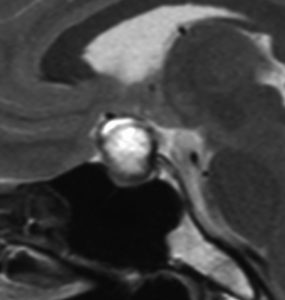

増大しても下垂体症状を出さなかった例

9歳の女の子に偶然発見された腫瘍です。何の症状もありませんでした。頭蓋咽頭腫と診断されて経過観察となりました。1年半観察しましたが腫瘍は増大して,視交差の変形が増して両耳側1/4半盲となり症候性となりました。下垂体機能は正常でした。

上のT2強調画像では,全体的に低信号で,高信号の部分が混在します。上右のCISS画像では,下垂体組織が右に変移していることが推定されます。

左がT1強調画像で高信号,右がT1ガドリニウム増強像ですが腫瘍は増強されません。正常か錐体が腫瘍の右側にくっついていて,ガドリニウム増強されています。典型的なトルコ鞍部黄色肉芽腫です。画像診断で,下垂体腺腫の腫瘍内出血とよく間違われるのですが,高信号になるのはコレステリン結晶を豊富に含むからです。ガドリニウム増強される部分がほとんどないという所見が頭蓋咽頭腫とは異なるところでしょう。